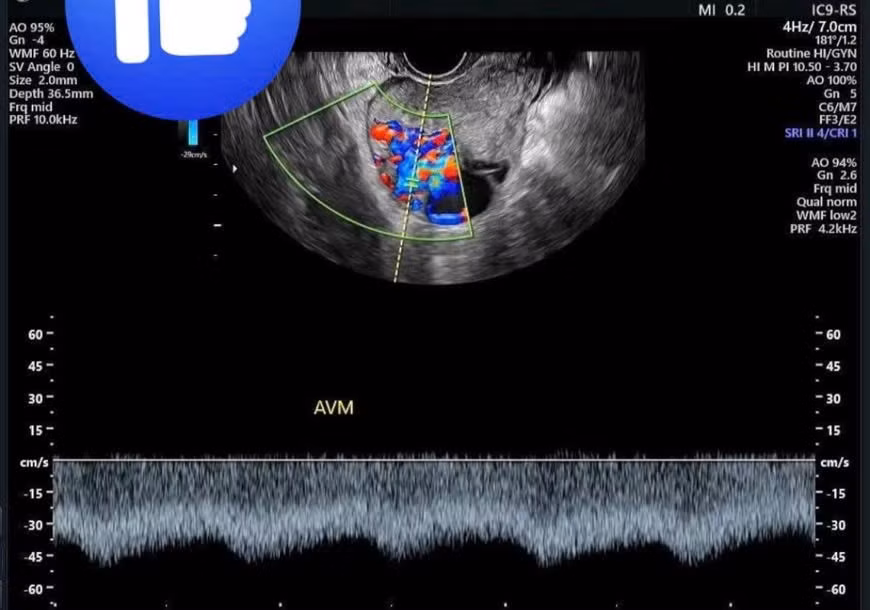

Qua siêu âm nghi ngờ tình trạng thông động tĩnh mạch tử cung, người bệnh tiếp tục được chụp cắt lớp vi tính tiêm thuốc cản quang phát hiện ổ thông động tĩnh mạch trong cơ tử cung kích thước 31x46mm, được cấp máu từ cả động mạch tử cung hai bên và động mạch buồng trứng; tĩnh mạch dẫn lưu về chậu và buồng trứng hai bên.

Hình ảnh thông động tĩnh mạch tử cung (AVM) qua siêu âm - Ảnh BVCC

Thông động tĩnh mạch (AVM) tử cung là bệnh lý hiếm gặp, là tình trạng nối thông bất thường giữa động và tĩnh mạch trong tử cung, tiềm ẩn nhiều biến chứng nguy hiểm. Nếu không được chẩn đoán và xử trí kịp thời, bệnh nhân có thể đối mặt với tình trạng xuất huyết nặng, thiếu máu trầm trọng, thậm chí đe dọa tính mạng.